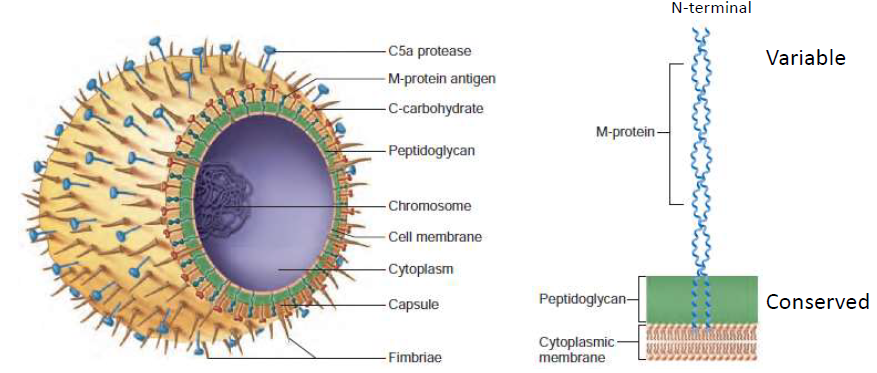

格蘭氏染色

Positive

- 單層膜

- Teichoic acid

Negative

- 雙層膜

- Lipopolysaccharide (LPS)

- Peptidoglycan

- Fimbriae

- 用來附著,不一定有

Streptococci (鏈球菌,G+)

- Catalase negative

- C-carbohydrate

- 細胞壁上多糖

- 區分 GAS, GBS

S. pyogenes (化膿性鏈球菌,GAS)

- Hyaluronic acid capsule (玻尿酸夾膜)

- M protein

- 用 emm gene 分類

- 抑制 C3b

- M-like proteins

- 抑制 C3b

- C5a peptidase